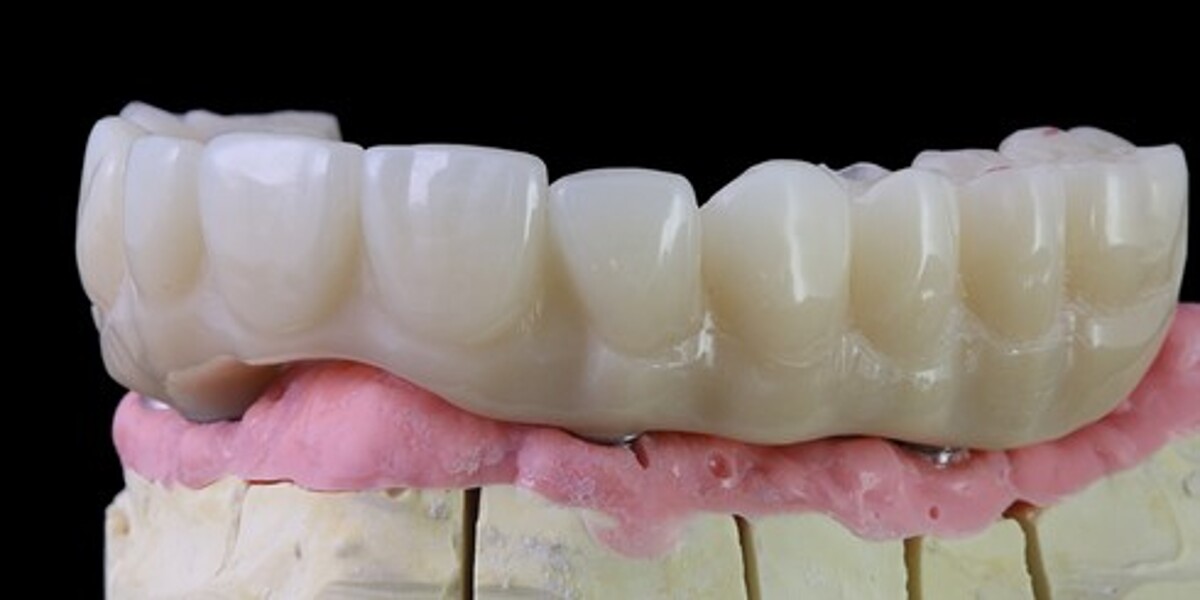

MAGICAL All on FOUR